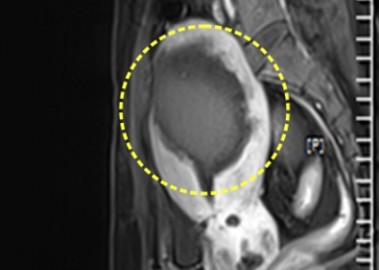

자궁근종 6cm 치료 전후